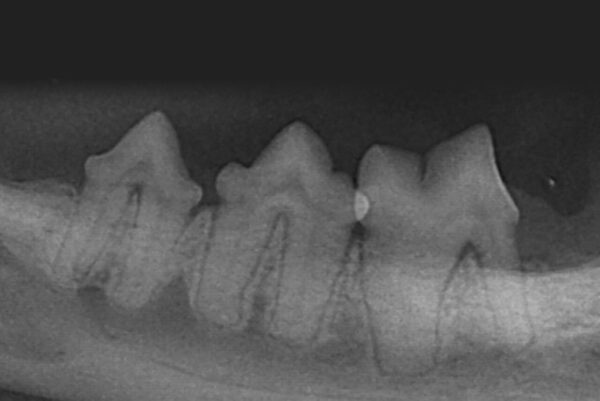

De acuerdo a esta pérdida del hueso alveolar detectada a nivel radiológico, clasificaremos la EP en cuatro grados:

- Grado 1 (PD1): sin pérdida ósea.

- Grado 2 (PD2): pérdida del soporte óseo menor al 25 % (imagen 7).

- Grado 3 (PD3): pérdida del soporte óseo de un 25-50 % (imagen 8).

- Grado 4 (PD4): pérdida del soporte óseo mayor de un 50 % (imagen 9).